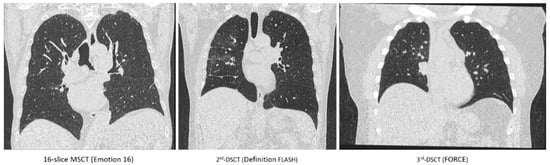

COPD Imaging on a 3rd Generation Dual-Source CT: Acquisition of Paired Inspiratory-Expiratory Chest Scans at an Overall Reduced Radiation Risk

2.1. Subjects, CT Systems, and Imaging Protocols